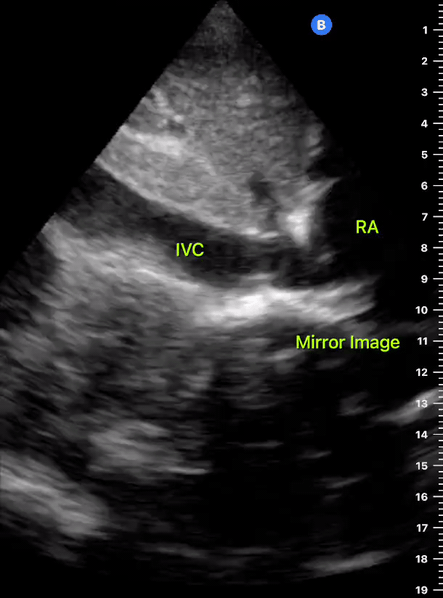

INFERIOR VENA CAVA VIEW

Coming from the subxiphoid view, scan longitudinally and slightly to the right of the body’s midline, with the orientation marker towards the head. Identify the landmarks and differentiate between the aorta and IVC by dragging the probe to the sides. Then slide the probe upwards, following the IVC as it traverses the diaphragm to enter the RA. Measure the IVC about 2 cm caudal to the RA entrance or 1 cm caudal to the hepatic vein inlet, but not at the level of the diaphragm. Measure the maximum IVC diameter, which will be in expiration, in two planes. Then measure the minimum IVC diameter using the sniff test: ask the patient to sniff quickly, causing the intrathoracic pressure to fall rapidly and a normal IVC to collapse. M-mode has been proposed to capture maximum and minimum diameters on a single image; however, this is not recommended, considering the IVC is displaced upwards with the respiratory movements (2).